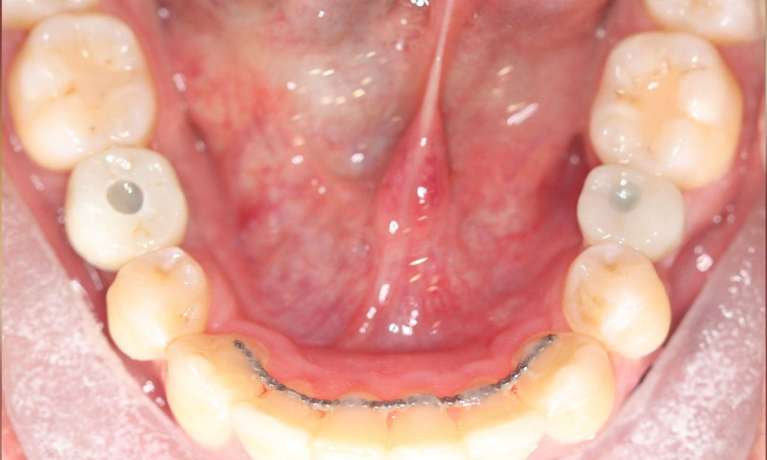

This patient came to us with some front teeth crowding, which was fixed with an Invisalign treatment. This gradually aligned the teeth leading to a straighter and more harmonious smile.